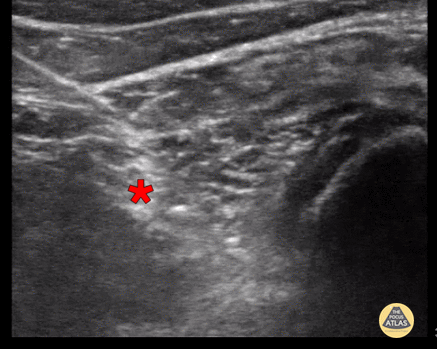

Popliteal Sciatic Nerve Block A 71 year old woman with dementia and mobility constraints presented with a gaping laceration over the posterior gastrocnemius extending inferiorly towards the achilles after a “fall from wheelchair”. Achilles tendon function was preserved and the wound was explored without foreign body. The patient did not tolerate initial attempts at laceration repair after local anesthesia due to pain and anxiety. A decision was made to perform a popliteal sciatic nerve block. The patient was placed in the prone position and 1% lidocaine without epi was drawn up in a syringe with extension tubing connected to a spinal needle under sterile conditions. A linear probe was used to identify the sciatic nerve just below the adductor magnus muscle. Lidocaine was injected 1 cm distal to the sciatic nerve’s bifurcation into the Common Peroneal N. and Tibial N. using the “in-plane” view. 20mL spread above, below and around the sciatic nerve sheath was sufficient to provide near-complete anesthesia and the patient tolerated the entire laceration repair. Submitted by Dr. Jordan Dow and Dr. Kelly Maurelus, Kings County Medical Center